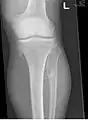

The diagnosis of HMO is based upon establishing an accurate correlation between the above-mentioned clinical features and the characteristic radiographic features. Family history can provide an important clue to the diagnosis. This is supplemented by testing for the two genes in which pathogenic variants are known to cause HMO namely EXT1 and EXT2. A combination of sequence analysis and deletion analysis of the entire coding regions of both EXT1 and EXT2 detects pathogenic variants in 70–95% of affected individuals.[3][4] The hallmark of radiographic diagnosis is the presence of osteochondromas at the metaphyseal ends of long bones in which the cortex and medulla of the osteochondroma represent a continuous extension of the host bone. This is readily demonstrable in radiographs of the knees.[3][1]

multiple osteochondromas around the knee